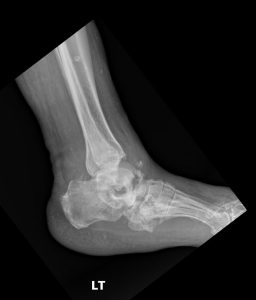

Radiographs are the workhorse for established Charcot. The classic findings are known as the “6 D’s”.

Interpreting these findings can be complex, especially in the early stages. The initial radiology report may be deceptively nonspecific, mentioning only “severe degenerative changes” or “comminuted fracture” without synthesizing these findings into the primary diagnosis of neuroarthropathy.

This is where Expert radiology consultation is critical. If the clinical picture suggests Charcot but the initial imaging is equivocal or the report is non-committal, do not hesitate to seek a Second opinion report. Specialist diagnostic imaging consultants—such as a musculoskeletal radiologist or a DACBR (Diplomate of the American Chiropractic Board of Radiology)—are trained to spot the subtle, early signs of neuropathic destruction.